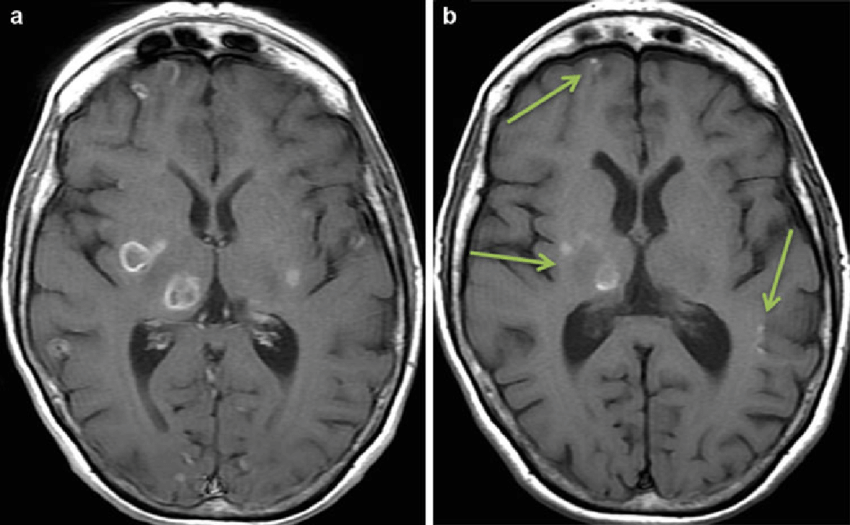

toxoplasmosis

tend to be in BG but can be anywhere

rim or nodular enhancement

often with surrounding edema